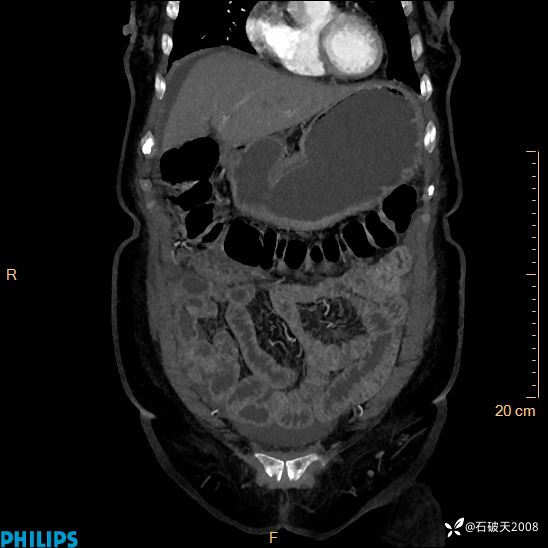

平扫